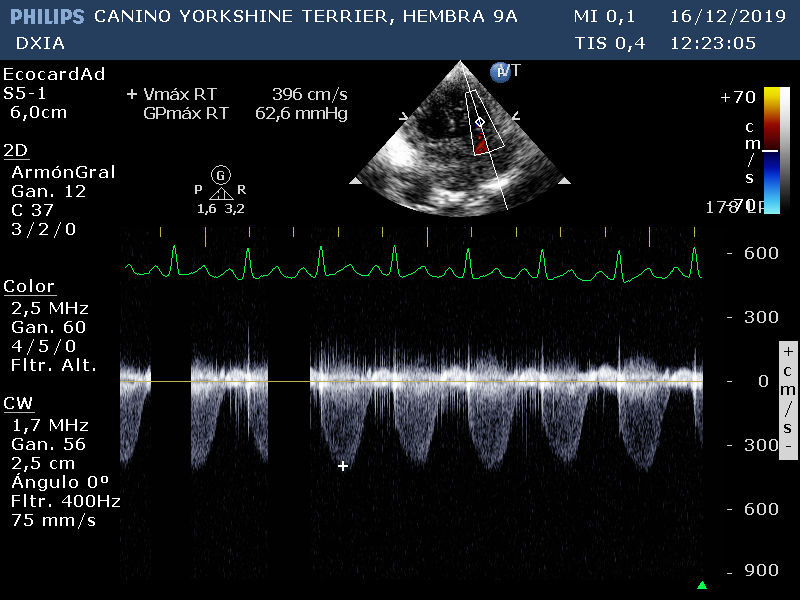

Corte apical izquierdo 4 cámras. Doppler tricúspideo. No se observan cambios en morfología de la VT. GP del flujo regurgitante de la VT mayor de 3 m/s, compatible con existencia de HP.